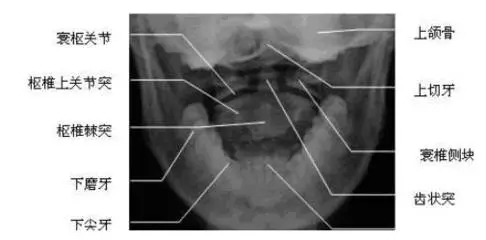

环枢关节错位,作恶多端,认识到它的人却不多。给大家提供一个方法:如果有上述症状,就可在风池穴、“后脑勺”处摸到肿胀,压痛剧烈,当然如果在耳下、下颌角后触摸到偏移的环椎横突或枢椎的棘突,那就可以盖棺定论了。确诊则需要拍颈椎的环枢椎张口位。